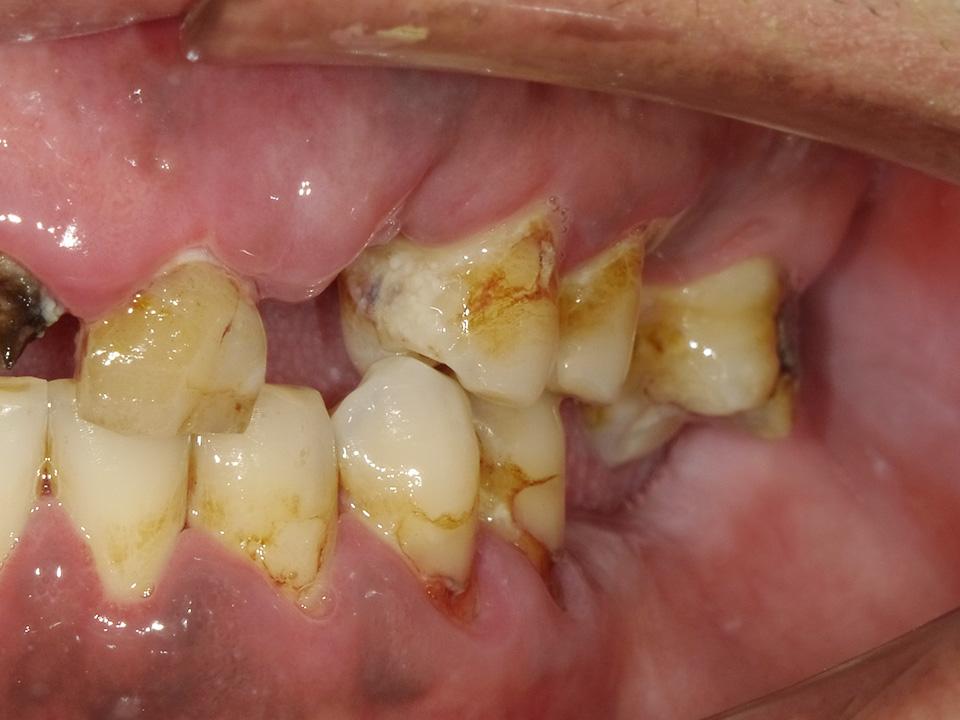

智能AI模擬右側照

智能AI模擬左側照